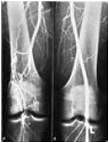

Angiografija

Kod pacijenata sa vijabilnim ekstremitetima, treba izvesti kontrastnu angiografiju radi dobijanja »road-map« za hirušku intervenciju. Time se identifikuje ne samo mesto okluzije nego i potencijalna mesta za proksimalni inflow i za distalnu anastomozu. Ako se nađe okluzija aorte i ilijačne arterija, hirurg će biti spreman za abdominalnu proceduru u slučaju neuspeha tromboembolektomije kateterom. Metoda je naročito korisna kod sumnje na arterijsku trombozu. Kod takvih pacijenata je malo verovatno da će trombektomija biti dovoljna, pa poznavanje arterijske anatomije može biti kritično za planiranje eventualnog bajpasa. Kako ova metoda odlaže operaciju obično za 2 - 3 h, pacijente sa ugroženim ekstremitetima, kao što su oni sa oslabljenom senzornom i motornom funkcijom, ne bi trebalo podvrgavati ovoj metodi, nego ih voditi pravu u operacionu salu.

Arteriografija

Dijagnostički može pomoći u razlikovanju embolusa i tromba. Embolus izgleda kao odsečan prekid stuba kontrasta ili u vidu znaka obrnutog meniskusa (»reverse meniscus sign«). Obično se viđa u arterijama koje inače izgledaju normalno. Tromb obično pokazuje ušiljenu (»tapering«) stenozu, sa evidentnom difuznom aterosklerozom i proksimalnih i distalnih arterija.